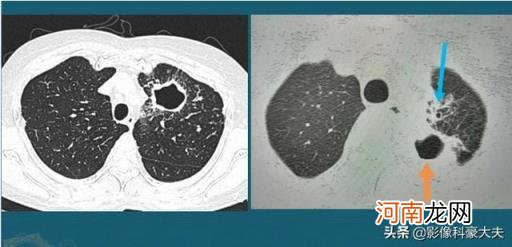

像这两个空洞样病灶,就是典型的肺结核,特点是空洞内壁光滑,周围有多种形态的卫星灶(索条影、粟粒状影,伴有支气管扩张) 。

因为肺结核杆菌含有大量脂肪成分,液化坏死以后可以与周围的钙离子发生皂化反应,形成脂肪酸钙,像肥皂颗粒一样具有清洁功能,加上结核杆菌的破坏比较彻底,所以肺结核的空洞常常比较光滑 。